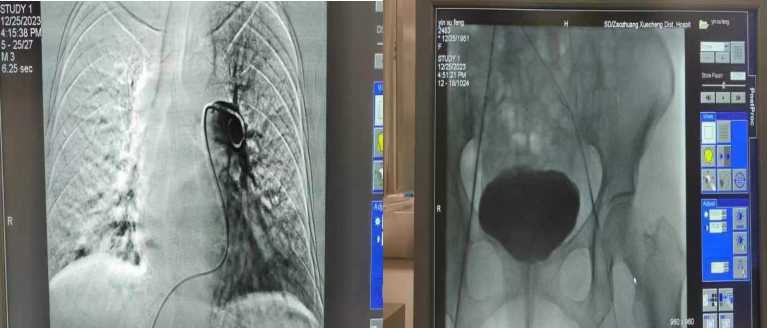

? 12月25日,我院多學科協(xié)作,完成首例肺栓塞介入治療,將患者從死亡邊緣搶救回來。

患者尹××,女,72歲,薛城本地人。 當日,患者因“憋喘明顯伴有左下肢腫痛2天”入住我院普外二科。入院時血氧飽和度在90%左右,急診行肺動脈 CTA及下肢血管超聲檢查,診斷為肺栓塞、左下肢深靜脈血栓形成,患者隨時出現(xiàn)生命危險。經(jīng)科室討論后迅速制定介入治療方案。由主治醫(yī)生王曦、劉國華在導管室急診實施手術:肺動脈造影+肺動脈血栓溶解劑灌注+下腔靜脈濾器置入+經(jīng)皮左下肢深靜脈吸栓術,手術時長1小時29分鐘。經(jīng)介入治療后,再次造影證實肺栓塞范圍較前縮小,患者喘憋癥狀明顯緩解,患肢腫脹程度減輕。截至目前,患者各項生命體征平穩(wěn),已能正常下床活動。